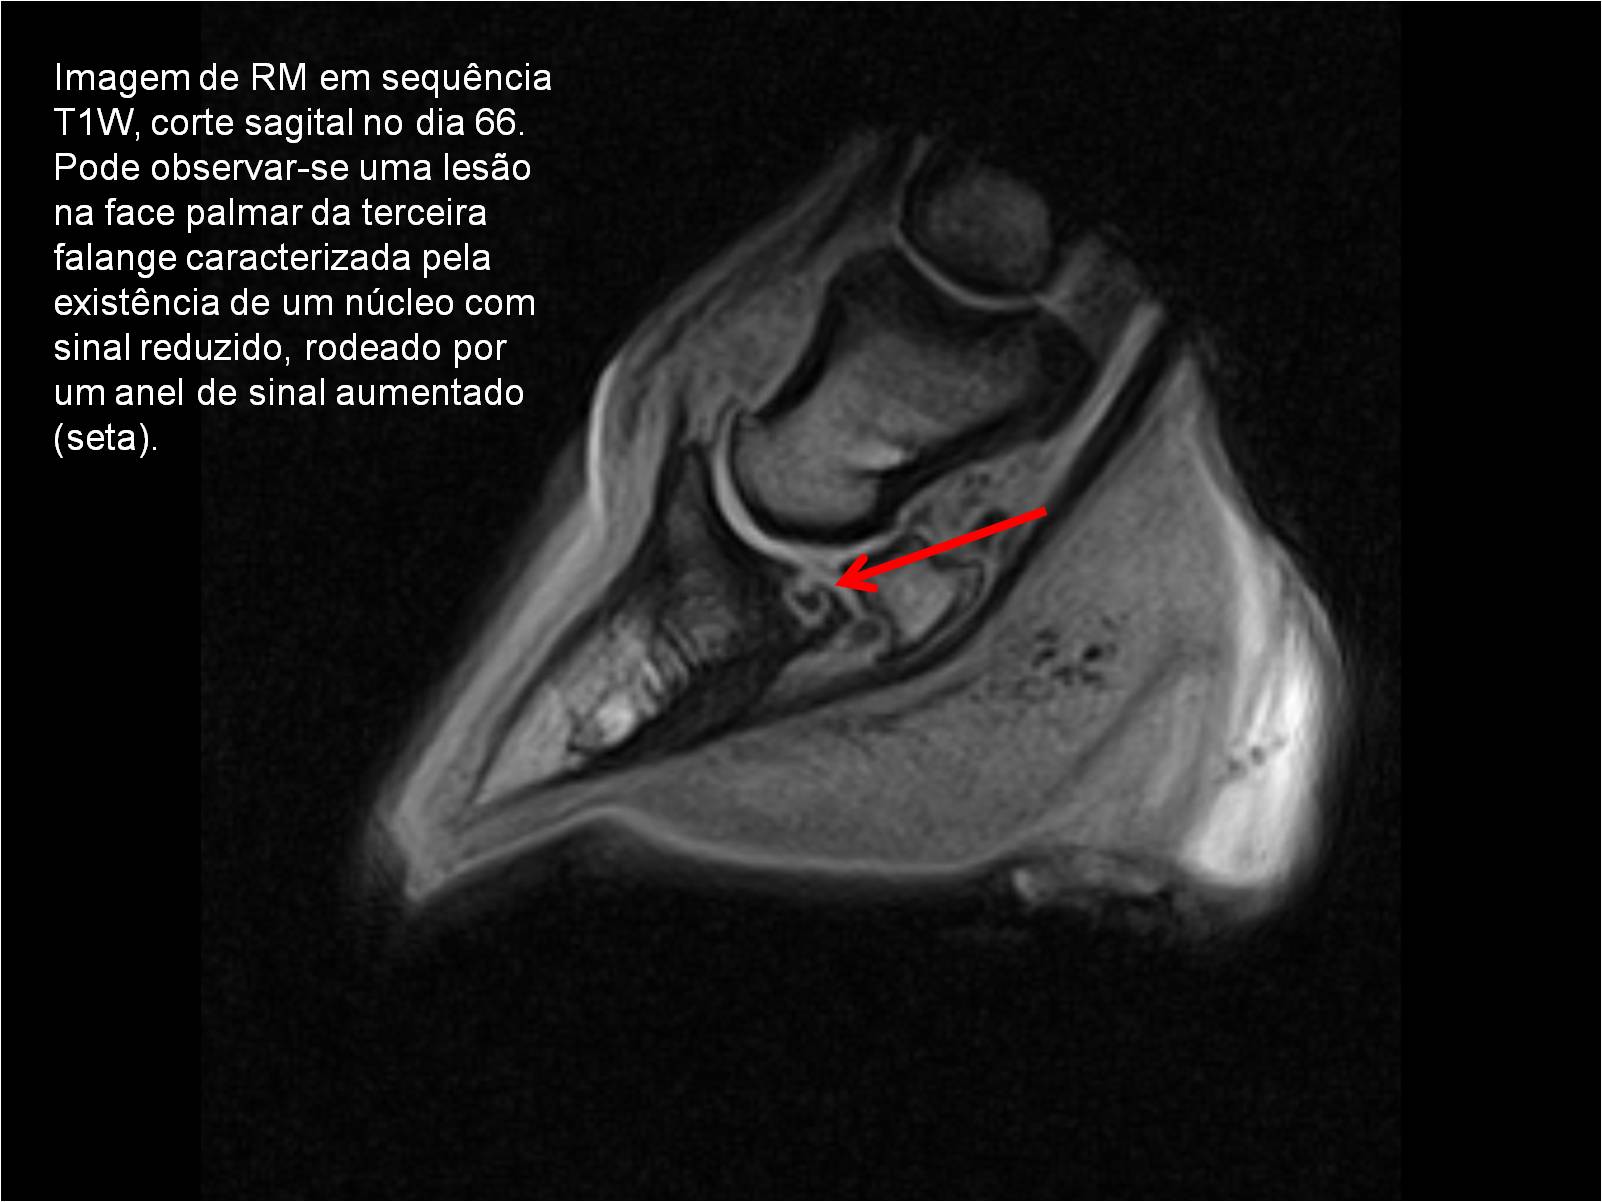

Publisher: Universidade de Évora

Abstract: O relatório de estágio encontra-se estruturado em três partes distintas. A primeira parte faz a caracterização das infraestruturas e funcionamento do Hospital Veterinário de Equinos de Lüsche, Oldenburg, Alemanha, assim como a análise casuística dos casos clínicos acompanhados durante os 6 meses de estágio. A segunda parte consiste de uma revisão bibliográfica sobre quistos do osso subcondral em equinos. Por fim, a terceira parte consta da apresentação e discussão de um caso clínico, nomeadamente o diagnóstico e acompanhamento imagiológico, por ressonância magnética, de um quisto subcondral na terceira falange num cavalo adulto; ### Abstract Equine Practice- Subcondral bone cyst of the third phalanx This internship report is divided in three parts. The first part characterizes the infrastructure and function of the Equine Hospital Lüsche, Oldenburg, Germany, as well as the casuistic of the clinical cases accompanied during the 6 month internship. The second part consists in a bibliographic review of cystic lesions of the subchondral bone in equines. The third part consists in a case report, the diagnostic and imagiological accompaniment, by use of magnetic resonance imaging, of a subchondral bone cyst in the distal phalanx of an adult equine.